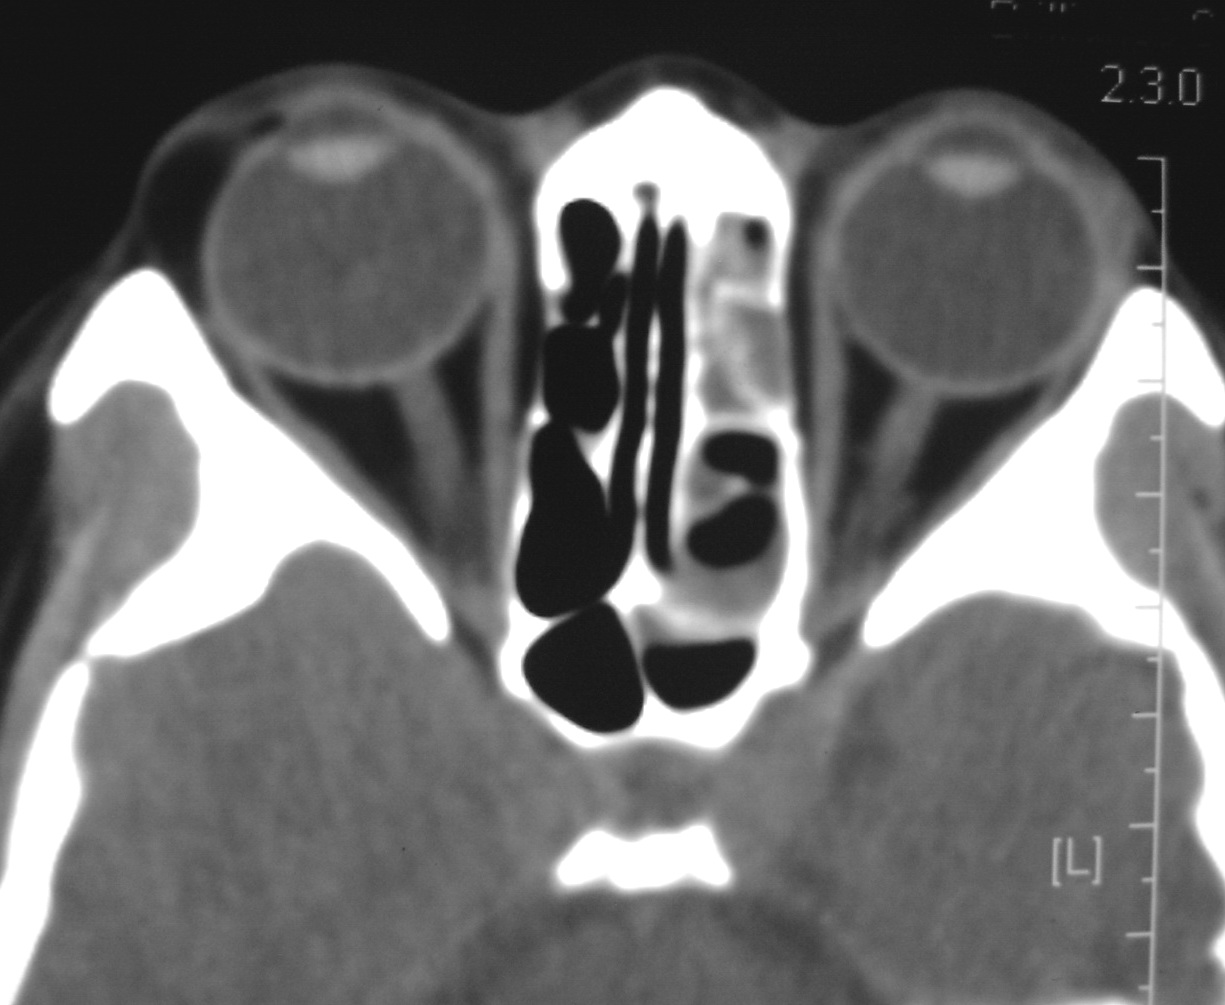

右侧眼眶脂肪瘤

女,34岁。右眼不适半年。

会员诊断:

表皮样囊肿、皮样囊肿、脂肪瘤

手术病理

:右侧眼眶

脂肪瘤

。